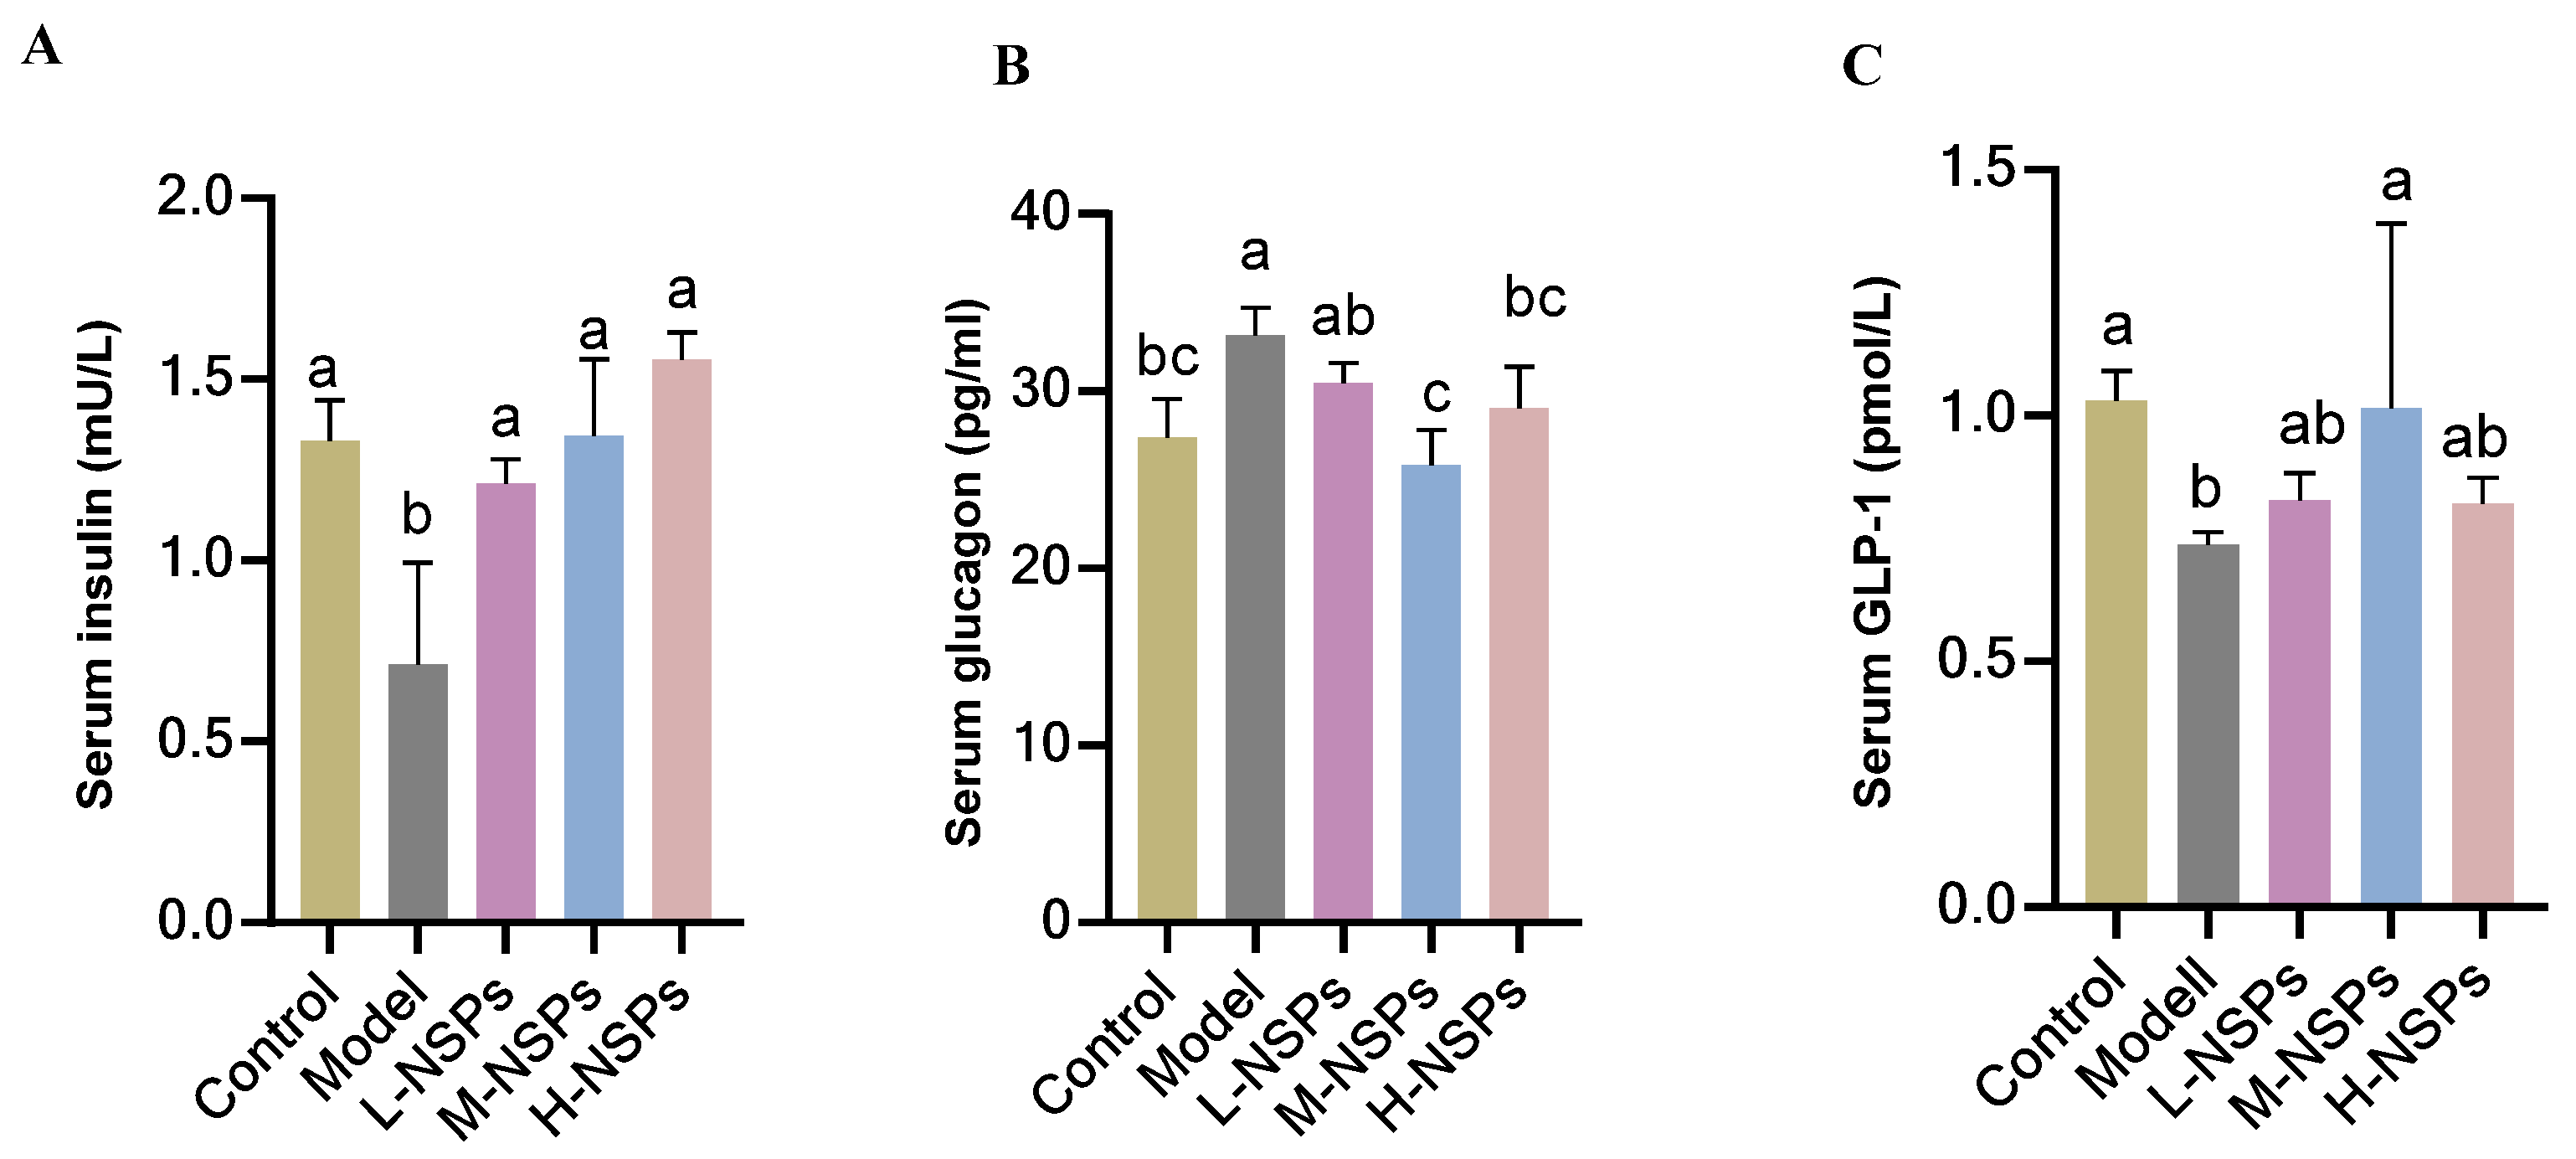

3.10. The Effect of NSPs on Serum Levels of Insulin, Glucagon, and Glucagon-like Peptide 1